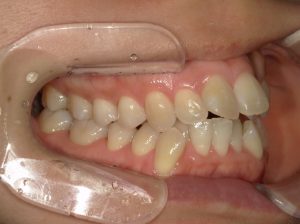

治療前→治療後(右側方)